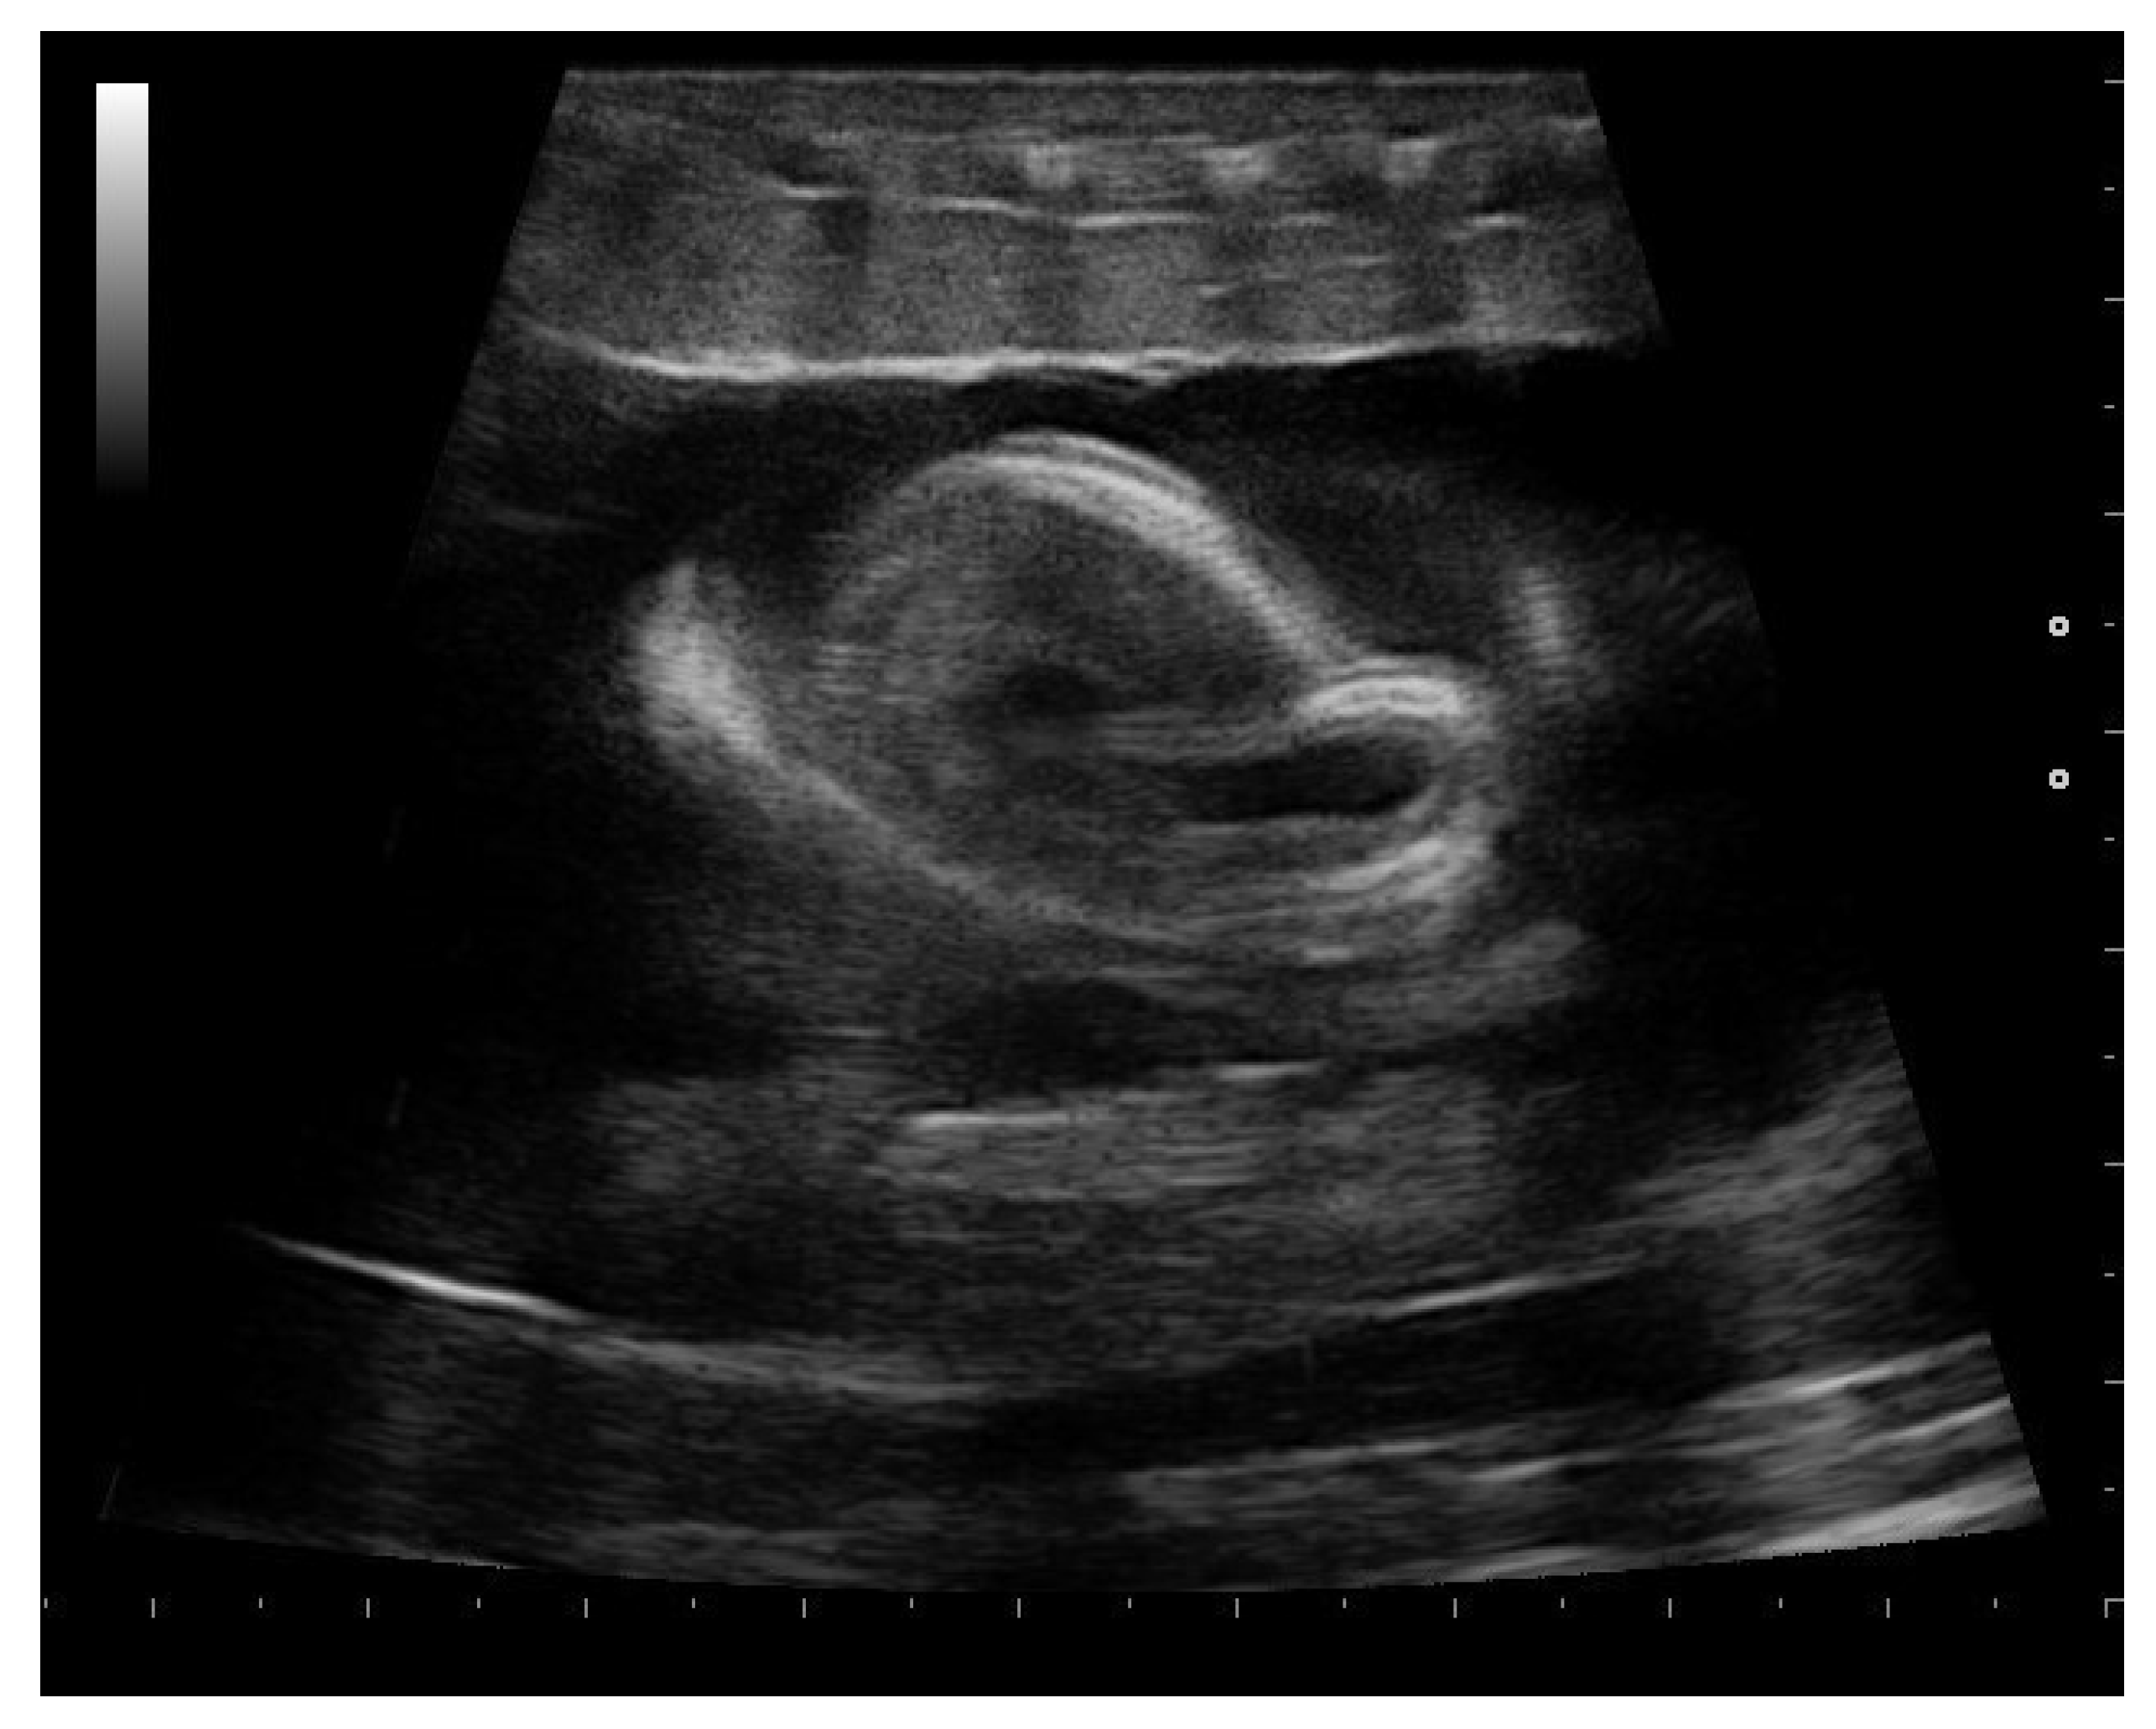

- Garcia, V.C.; Almeida-Santos, S.M. Reproductive cycles of neotropical boid snakes evaluated by ultrasound. Zoo Biol. 2021, 1–10. [Google Scholar] [CrossRef]

- Isaza, R.; Ackerman, N.; Jacobson, E.R. Ultrasound imaging of the coelomic structures in the Boa constrictor (Boa constrictor). Vet. Radiol. Ultrasound 1993, 34, 445–450. [Google Scholar] [CrossRef]